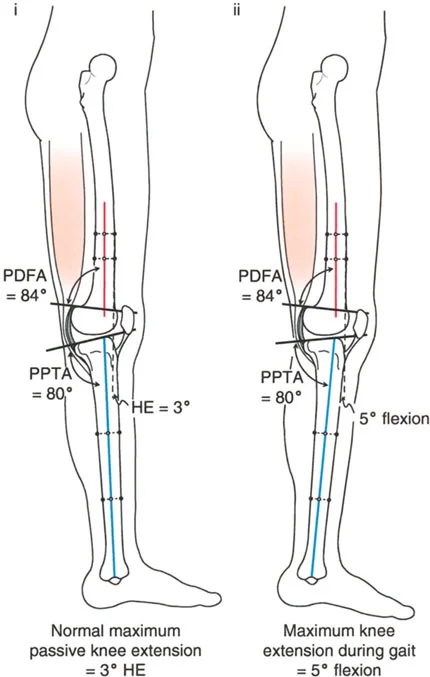

- الأشعة الجانبية الطويلة للطرف السفلي بالكامل أثناء الوقوف في أقصى بسط (Standing Long-Leg Lateral View in Maximum Extension): تُستخدم لتقييم تحدد حركة الركبة (FFD) والركبة الارتدادية (Recurvatum)، وتحديد ما إذا كان التشوه عظميًا أو ناتجًا عن تقلص في الأنسجة الرخوة.

الركبة الارتدادية هي فرط البسط في الركبة. غالبًا ما تكون غير مصحوبة بأعراض في الأشخاص ذوي العضلات السليمة، ولكنها قد تسبب مشاكل في حالات ضعف العضلات أو التشوهات العظمية.

- التشخيص: يجب تحديد ما إذا كانت الارتدادية عظمية (تقوس خلفي في الفخذ أو الساق) أو ناتجة عن رخاوة في الأنسجة الرخوة أو ضعف عضلي.